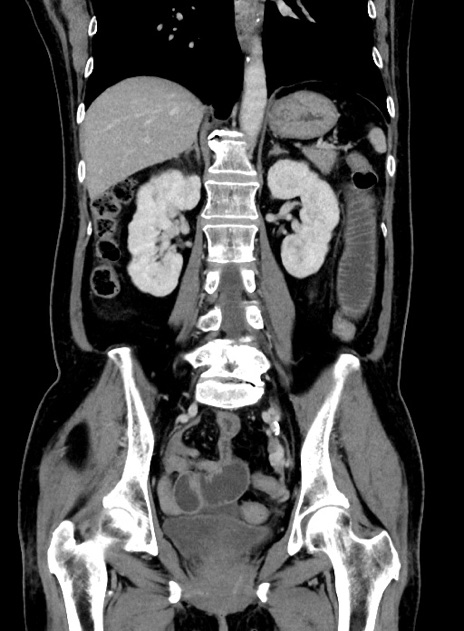

症例9(冠状断像)

【症例】 60歳代女性

【主訴】むかつき、みぞおちの痛み

【現病歴】3日前よりむかつきがあり、食事がとれない。

【既往歴】糖尿病

【身体所見】発熱なし、心窩部圧痛軽度あるも、腹膜刺激症状なし。

【データ】WBC 7400、CRP 1.92